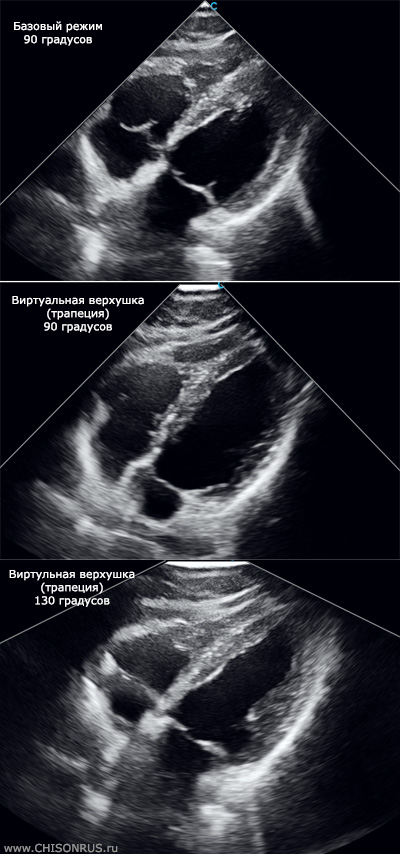

Пример на одном пациенте:

При стандартном сканировании на секторных фазированных кардиологических датчиках сектор сканирования обычно представляет собой угол 90 градсов. Ультразвуковое изображение исходит из верхушки в форме точки. По этой причине в ряде случаев сердце сложных пациентов или с патологией (гипертрофия) может не помещаться на экран - не хватает сектора сканирования.

Виртуальная верхушка представляется собой трапециевидное сканирование на фазированном датчике. Таким образом угол сканирования сохраняется (90 градусов), но за счет трапеции появляются боковые зоны сканирования. При этом скорость сканирования (FPS) не уменьшается, а качество сканирования практически не падает (в отличие от режимов где увеличивается сам угол сканирования с 90 до 120 градусов).

2) Расширенный угол сканирования (сектор сканирования в таком случае расширяется с 90 до 130 градусов).